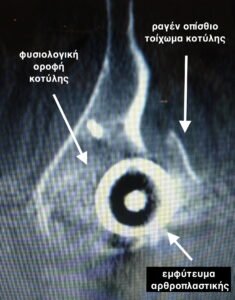

- Τρισδιάστατη αξονική τομογραφία (παράσιτα λόγω εμφυτεύματος) δείχνει την αποκόλληση του εμφυτεύματος της κοτύλης και την οπίσθια μετατόπιση του , μαζί με το κάταγμα του οπισθίου τοιχώματος της κοτύλης.